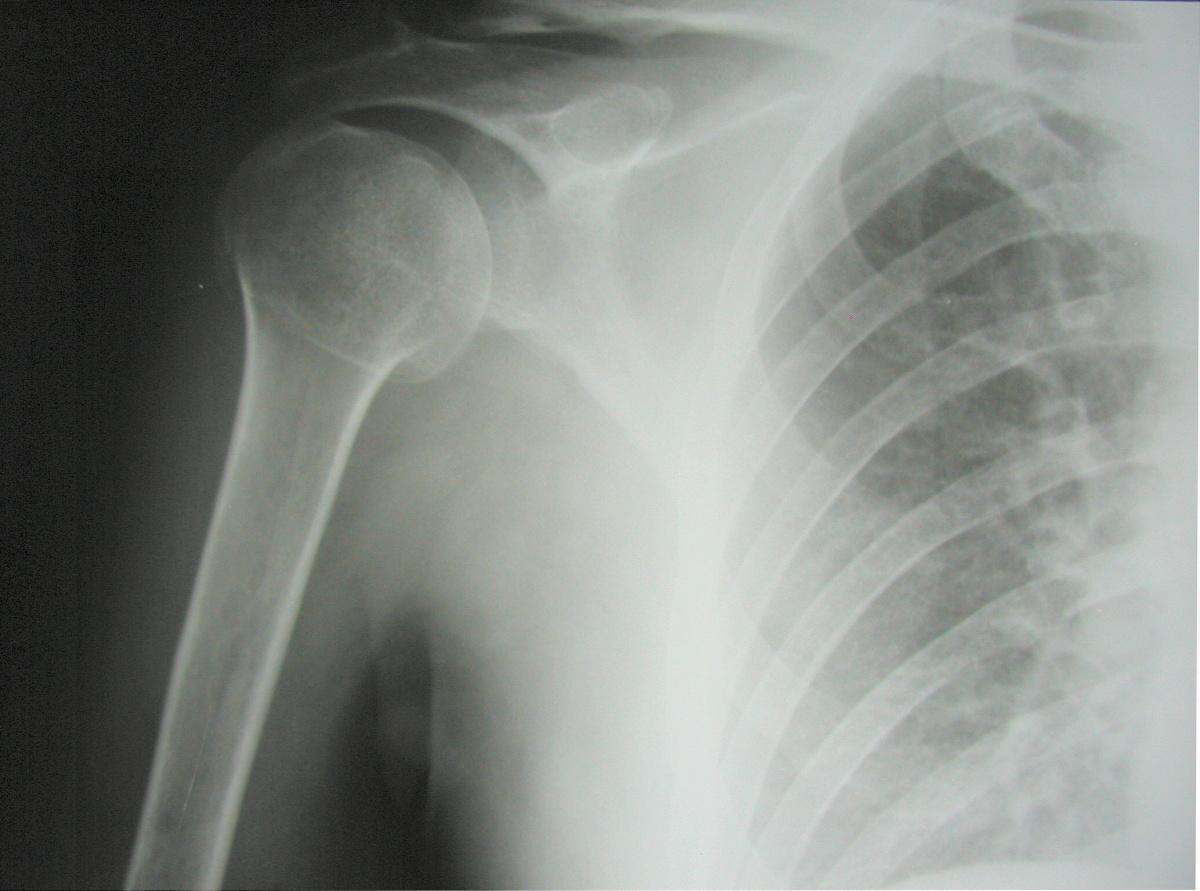

Fractures extra-articulaires

Fracture du tubercule majeur et mineur ou du col chirurgical :

- non déplacée : traitement orthopédique par coude au corps pendant 4 semaines et contrôle radiologique à J7-J10.

- déplacée : avis chirurgical.

Fractures articulaires

C’est à dire au niveau du col anatomique, encore appelées fractures céphaliques : risque de nécrose ++ → avis chirurgical.